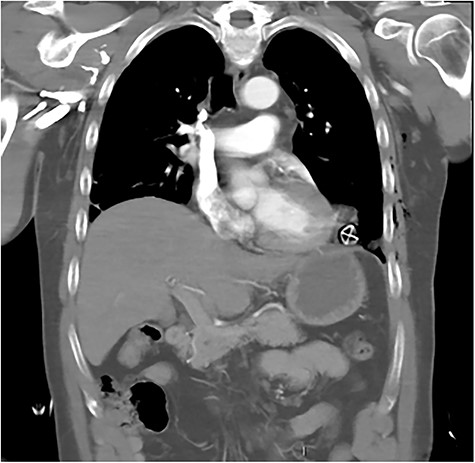

After primary survey and usual trauma imaging showed no air of fluid in either hemithorax, the patient underwent an emergent computed tomography (CT), which revealed a metal pole traversing the left hemithorax penetrating to the posterior chest wall at the level of the ninth rib. The metal pole was abutting the pericardium and was touching the posterior chest wall (Figs 1, 2 and 3).

CT coronal image showing solar powered garden light proximity to diaphragm and cardiac border.